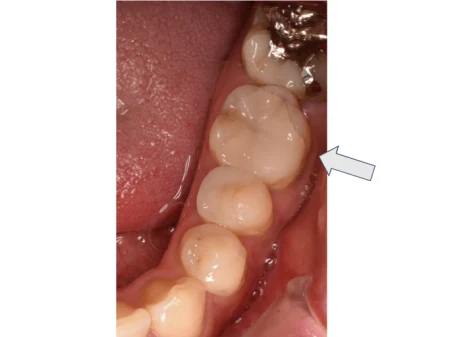

セラミック 2023.0330代男性「左下の詰め物が欠けた」透明感のある白さで耐久性の高いガラスセラミック「e-max」で綺麗に作り直した症例